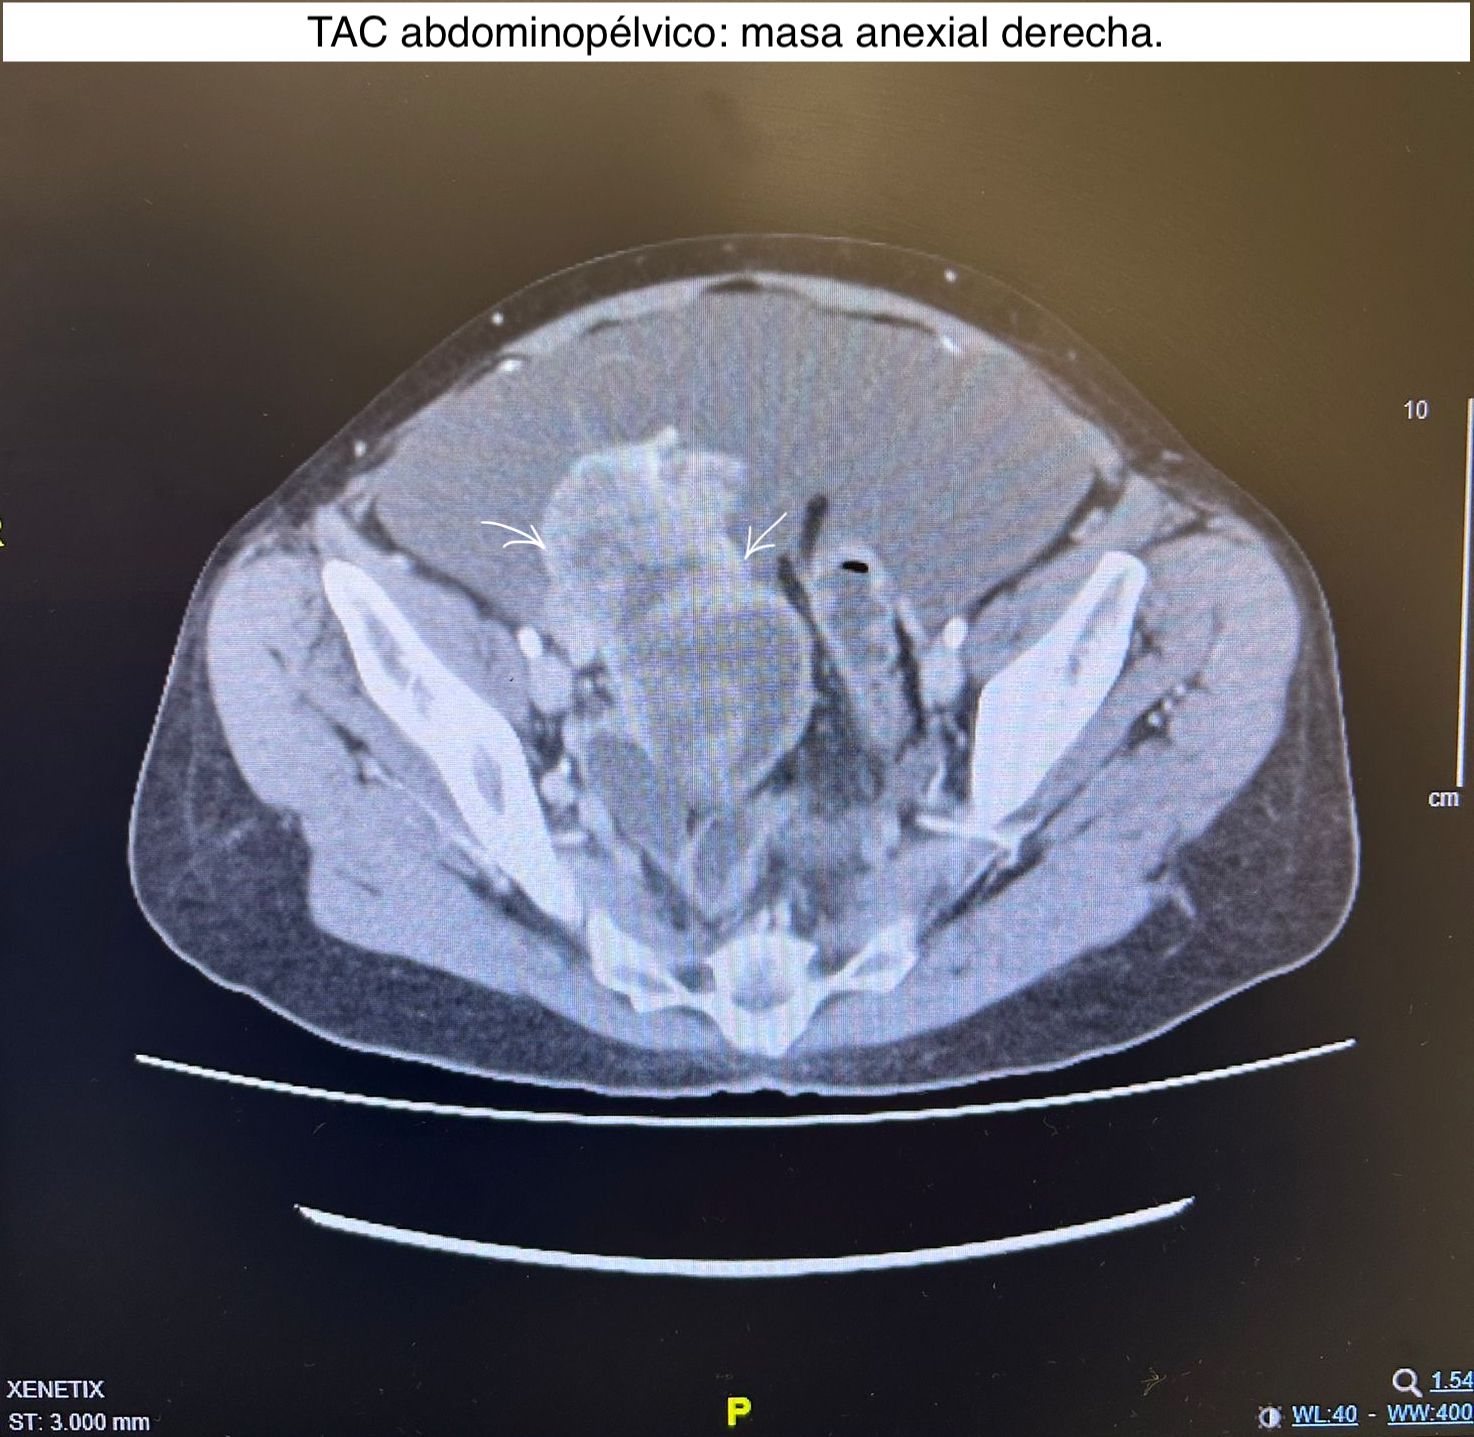

Para evaluar la propagación de la patología se solicita TAC abdomino-pélvico con contraste confirmando el hallazgo de lesión de probable origen anexial derecho con infiltración del mesenterio del íleon y del ligamento redondo hepático, carcinomatosis peritoneal, ascitis, lesiones omentales y capsulares hepáticas.